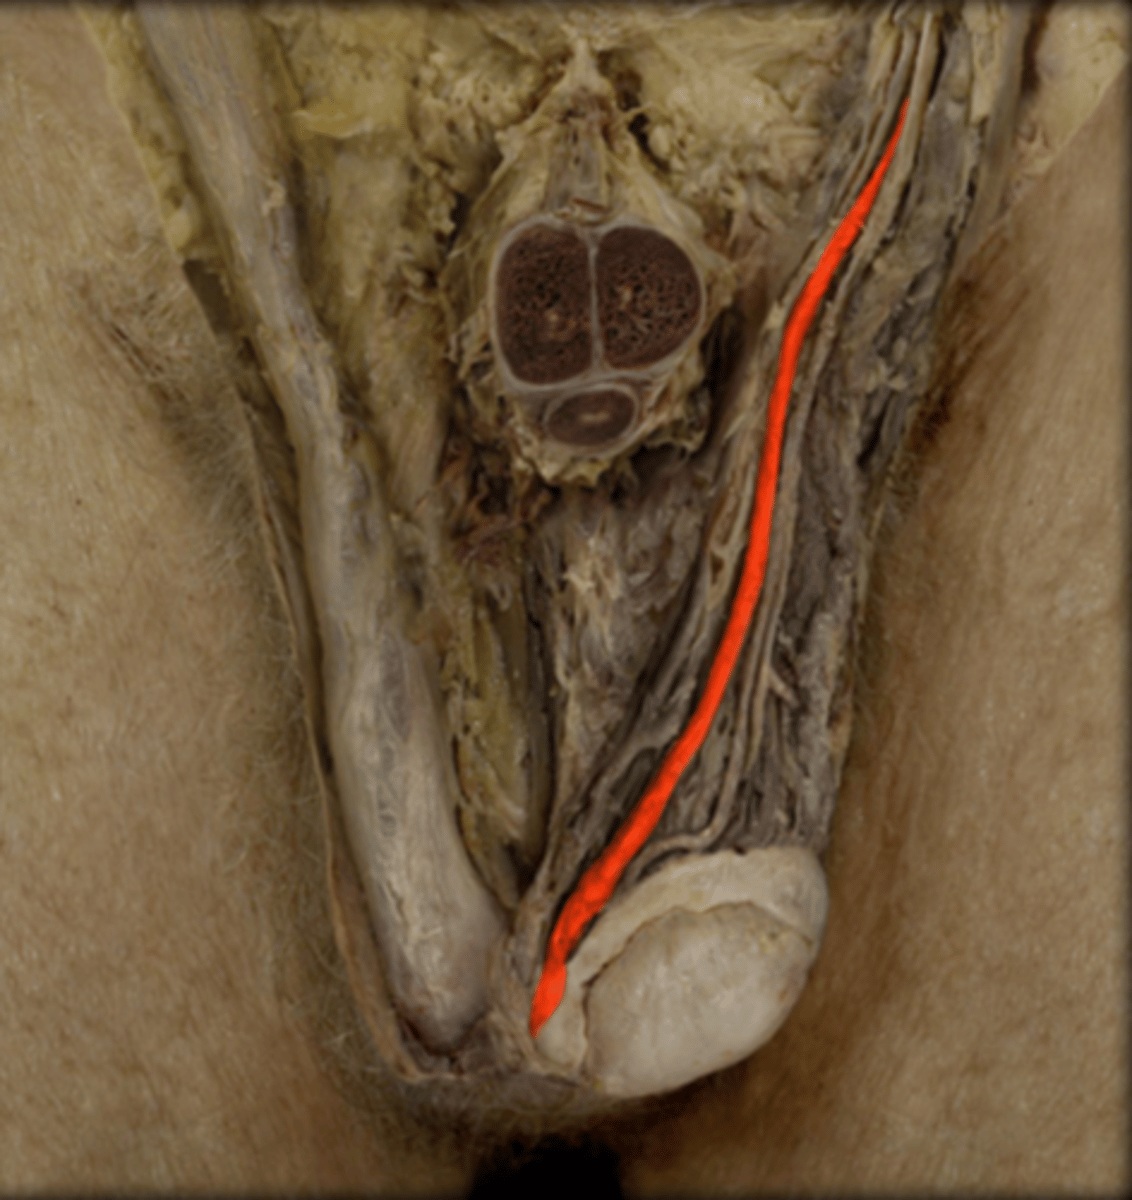

Testis

Epididymis

Spermatic Cord

Vas Deferens

Penis

Corpus Cavernosum

Glans Penis